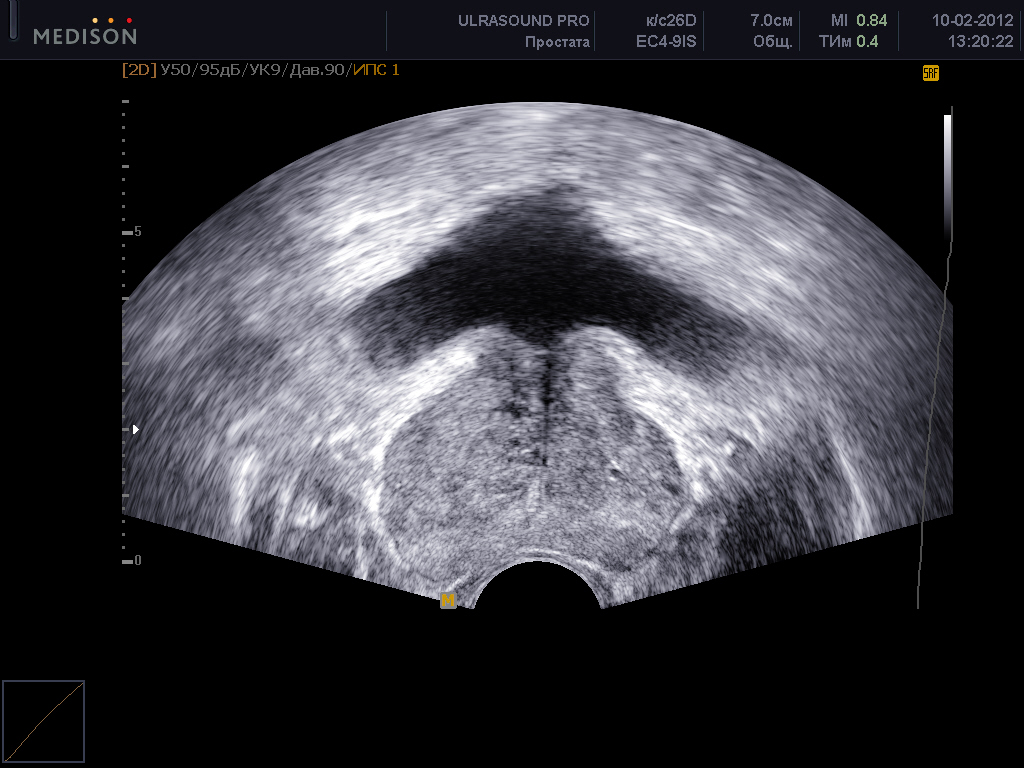

Простата, обычно ассоциируемая с мужским здоровьем после полового созревания, также присутствует у детей, хотя и в значительно меньших размерах. Этот орган, расположенный под мочевым пузырем и окружающий уретру, играет роль в выработке жидкости, которая составляет часть семенной жидкости. Несмотря на то, что проблемы с простатой у детей встречаются редко, понимание её развития и потенциальных патологий важно для ранней диагностики и лечения.